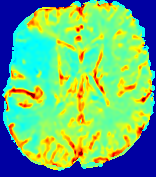

TimeSlice(i)(ii)(iii)(iv)(v)(vi)Refer to caption00555101010151515202020252525Refer to caption(a)(b)Refer to captionRefer to captionRefer to captionRefer to captionRefer to captionRefer to captionRefer to captionRefer to captionRefer to captionRefer to captionRefer to captionRefer to captionRefer to captionRefer to captionRefer to captionRefer to captionRefer to captionRefer to caption(a)(b)Refer to captionRefer to captionRefer to captionRefer to captionRefer to captionRefer to captionRefer to captionRefer to captionRefer to captionRefer to captionRefer to captionRefer to captionRefer to captionRefer to captionRefer to captionRefer to captionRefer to captionRefer to caption(a)(b)Refer to captionRefer to captionRefer to captionRefer to captionRefer to captionRefer to captionRefer to captionRefer to captionRefer to captionRefer to captionRefer to captionRefer to captionRefer to captionRefer to captionRefer to captionRefer to captionRefer to captionRefer to caption(a)(b)Refer to captionRefer to captionRefer to captionRefer to captionRefer to captionRefer to captionRefer to captionRefer to captionRefer to captionRefer to captionRefer to captionRefer to captionRefer to captionRefer to captionRefer to captionRefer to captionRefer to captionRefer to caption(a)(b)Refer to captionRefer to captionRefer to captionRefer to captionRefer to captionRefer to captionRefer to captionRefer to captionRefer to captionRefer to captionRefer to captionRefer to captionRefer to captionRefer to captionRefer to captionRefer to captionRefer to captionRefer to caption(a)(b)Refer to captionRefer to captionRefer to captionRefer to captionRefer to captionRefer to captionRefer to captionRefer to captionRefer to captionRefer to captionRefer to captionRefer to captionRefer to captionRefer to captionRefer to captionRefer to captionRefer to captionRefer to caption

Figure 6: Predicted concentration time series for the same patient shown in Fig. 4, where (i)-(vi) correspond to slices #1-6 respectively. Each grouped row displays (a) the measured concentration image sequences and (b) the predicted concentrations at corresponding time points.

3.2 Predicted CA Concentration

To better illustrate the prediction accuracy, and therefore the estimation accuracy of 𝐕𝐕{\bf V} and D𝐷{D}, of PIANO, we provide the corresponding predicted time-series of CA concentration images in Fig. 5 and Fig. 6 for the same patients in Fig. 3 and Fig. 4, respectively. We see that PIANO is capable of predicting the CA concentration given their initial state, indicating its ability to successfully capture 𝐕𝐕{\bf V} and D𝐷{D}. Note that although the concentration values for these two patients differ considerably, caused by the different total volume of injected CA, PIANO is still able to provide plausible estimates.